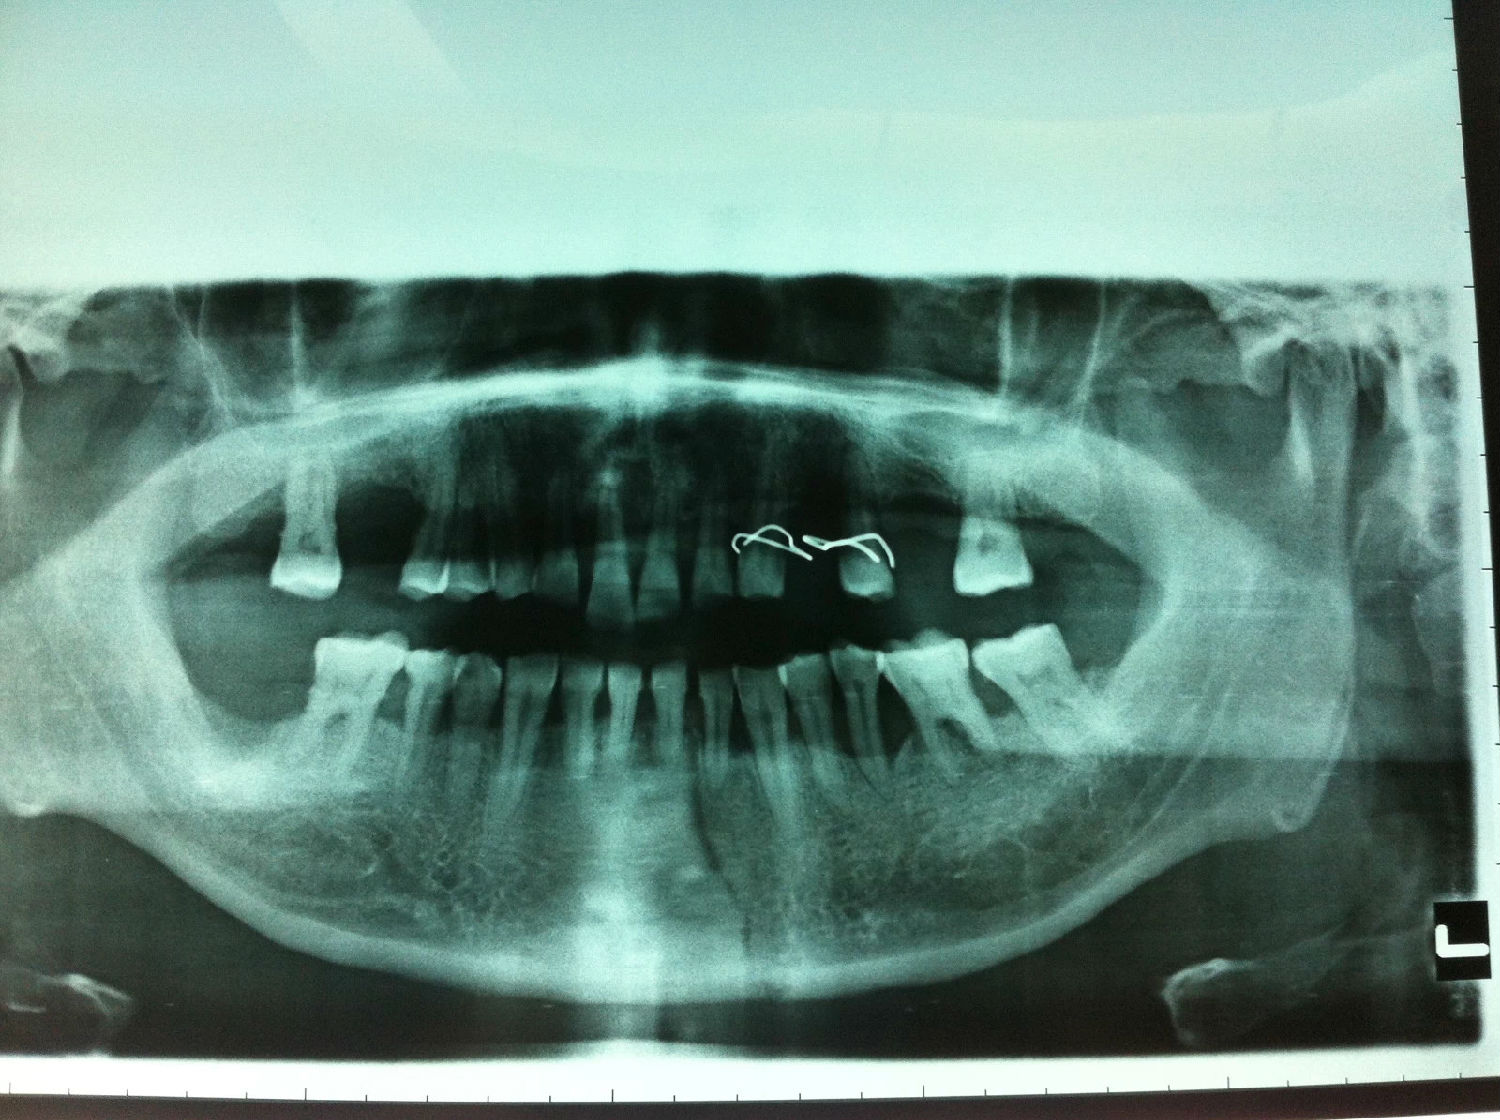

入院后全麻下手術(shù)治療,左側(cè)下頜骨囊腫較大,術(shù)前考慮病理性骨折可能,準(zhǔn)備鈦釘鈦板固定,術(shù)中摘除囊腫后,發(fā)現(xiàn)下頜骨下緣骨量尚可,未給予固定。術(shù)后病理診斷為下頜骨角化囊腫,考慮到患者可能為基底細(xì)胞癌綜合征,術(shù)中切除頸部皮膚痣兩處,術(shù)后病理診斷為:皮膚痣,排除基底細(xì)胞癌綜合征?;颊哂凶髠?cè)第六肋骨分叉肋,綜合以上特征,最終診斷為多發(fā)性頜骨囊腫綜合征。